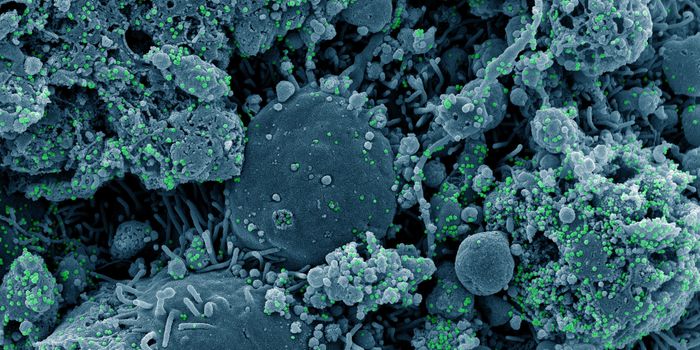

SEP 25, 2021Health & MedicineAfter a year-long study, researchers have assembled a detailed narrative about how the SARS-Cov-2 virus has spread on th ...